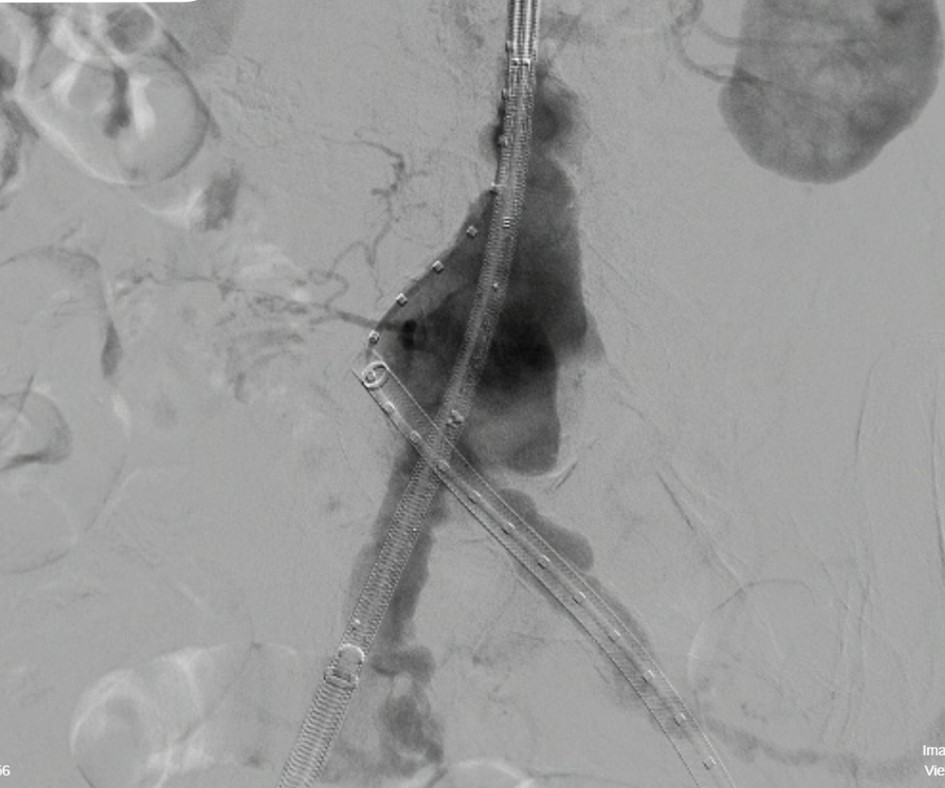

Ca can thiệp cho bệnh nhân - Ảnh BVCC

Sau hội chẩn chuyên môn, ê-kíp bác sĩ quyết định thực hiện đặt Stent Graft động mạch chủ bụng dưới hướng dẫn của hệ thống DSA.

Phương pháp can thiệp này chỉ gây tê tại chỗ, tiền mê nhẹ. Sau đó can thiệp qua đường động mạch đùi bằng một lỗ chấm nhỏ, tạo lòng mạch mới vững chắc, loại bỏ áp lực máu lên túi phình

Ca can thiệp diễn ra thuận lợi trong khoảng 1,5h. Bệnh nhân hồi phục nhanh, sinh hiệu ổn định và được xuất viện sau 3 ngày theo dõi, trong tình trạng sức khỏe tốt.